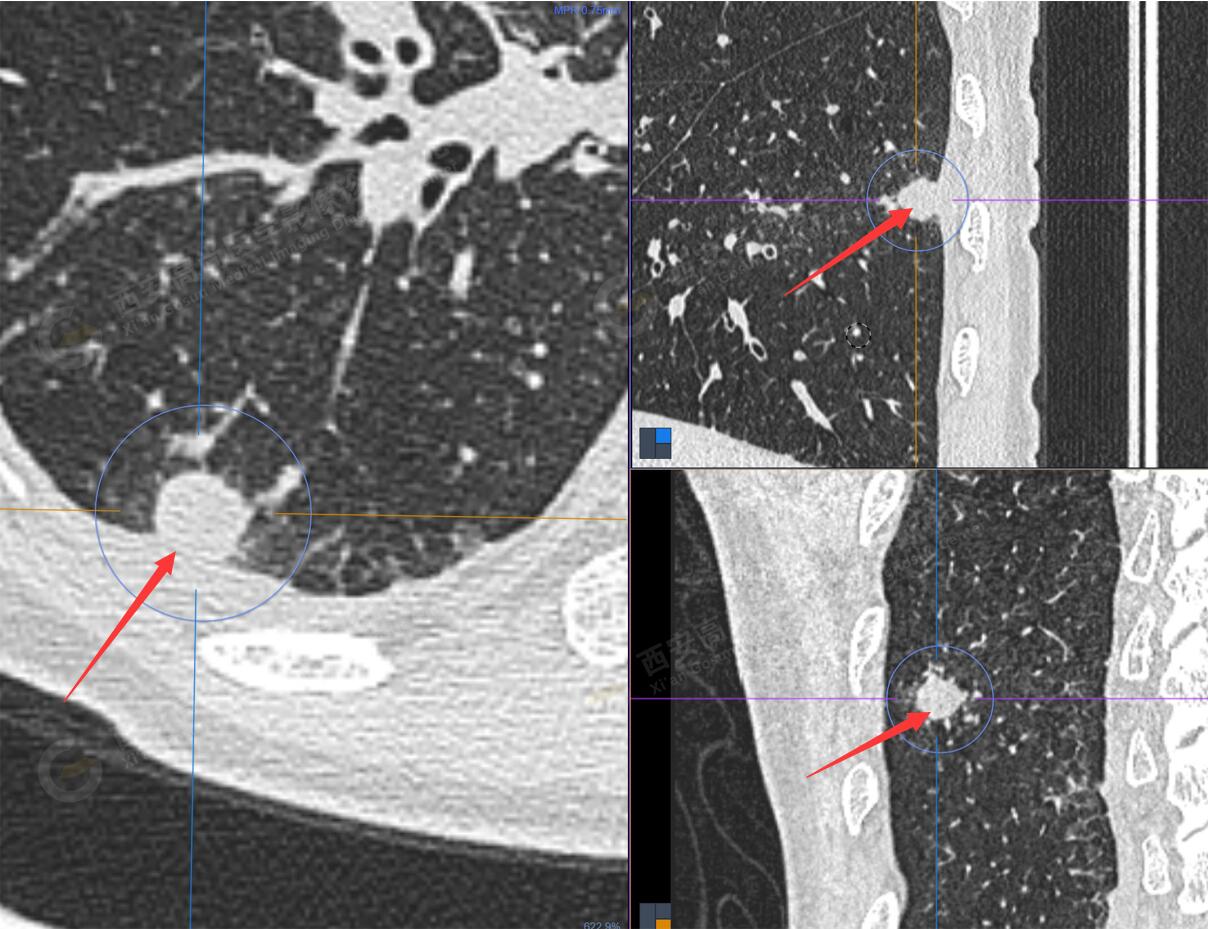

1.以下為肺內(nèi)原發(fā)灶

1.右肺下葉后基底段軟組織結(jié)節(jié)(約1.5cm×1.2cm),與相鄰后胸膜分界不清,呈FDG代謝異常增高,結(jié)合病理,符合肺腺癌伴鄰近胸膜侵犯。